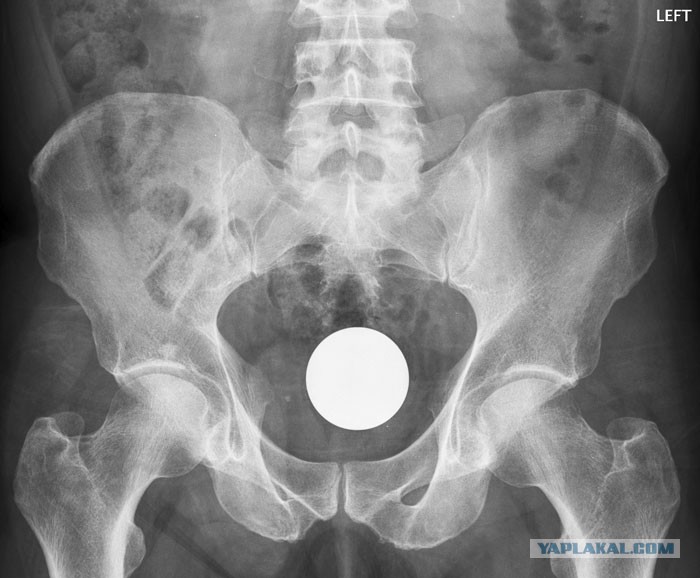

во, типа такого:

Шар №12